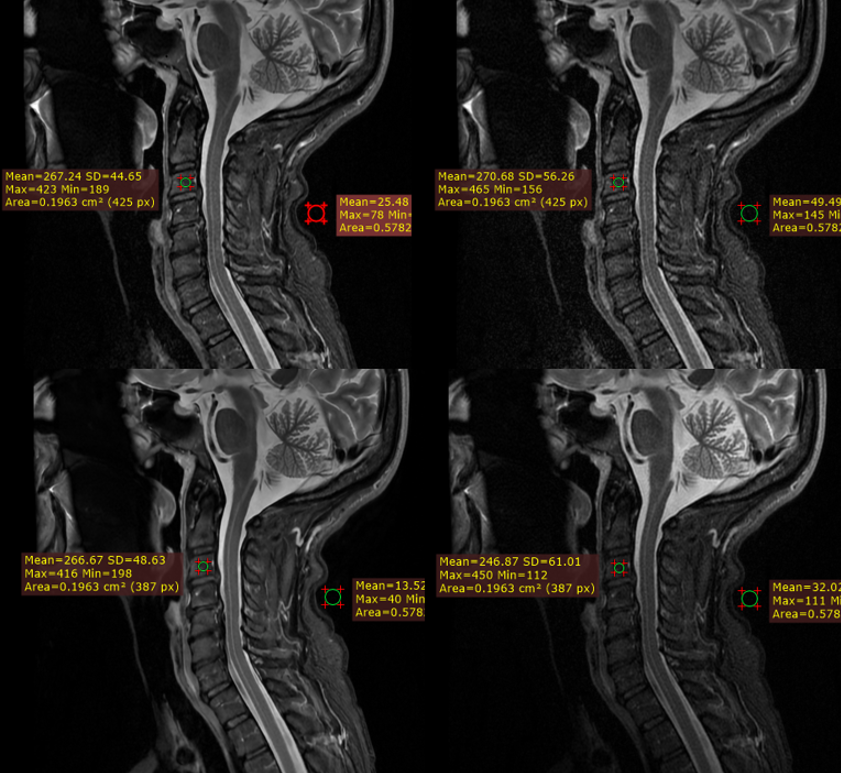

Figure 3 depicts a T2 weighted STIR image acquired with a matrix of 320 224 (top left) reconstructed with AirReconDL™ and the same image reconstructed conventionally (top right). The strength of the algorithm was set to “medium”. Upon acquiring and inspecting the image, we could not be sure if the line with the brighter signal was an artifact that resembles syringomyelia, or whether it was a finding. Therefore, we increased the resolution to 384x288, and set the strength of the algorithm to “high”, and increased the echo train length by 2, leading to a slight increase in acquisition time of 14 seconds, but with a final image of far superior image quality (bot left). This way, we were able to conclude that it was a normal finding, and neither an artifact nor a pathology. Same image reconstructed conventionally can be seen on the bot right.

![[Uncaptioned image]](/html/2206.01082/assets/Figure_3.png)

Figure 3. Sagittal fast spin echo STIR images. Top row has AirReconDL™ strength set to medium with an acquisition matrix of 320x224. Bottom row has AirReconDL™ strength set to high, and acquisition matrix of 364x288, increased echo-train length by 2. Images on the left are reconstructed through the DL-based pipeline, and images on the right are reconstructed conventionally. SNR gains were 192% (top row), and 256% (bot row).